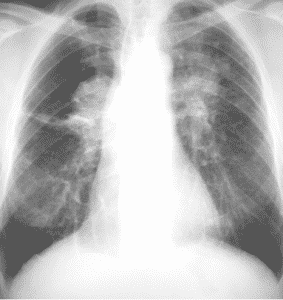

Granulomas y conglomerados (Silicosis)